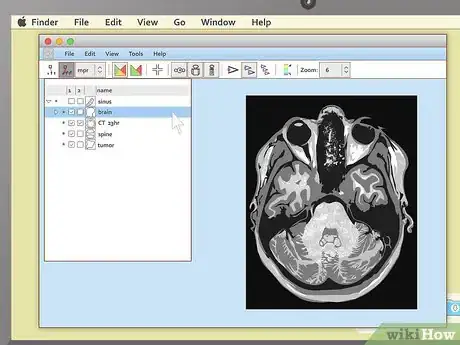

4Load the study. Again, the exact steps you'll need to take here can vary slightly depending on the exact program you have packaged with your images. Generally, most MRI viewers will have some sort of option to load or import images that you can select from the menu bar at the top of the screen. In this case, select this option, then pick the image file on your disc that you'd like to look at.

- Note that most medical imaging software refers to collections of images as "studies". You may not see an "import image" option, but you'll probably see something to the effect of "import study."

- Another option you may encounter is that, as soon as the program loads, it will present you with a "table of contents" of all the MRIs on the disc. In this case, simply select the study you want to view first to proceed.

3Use cross-sectional views to spot abnormalities in brain MRIs. MRIs of the brain tissue are often used to check for brain tumors, abscesses, and other serious problems that can affect the brain. The easiest way to see these things is usually to choose the cross-sectional view, then descend slowly from the top of the head downward. You're looking for anything that's not symmetrical — a dark or light patch that's on one side but not the other is cause for concern.

- Brain tumors often take the form of round, golf ball-like growths in the brain which will usually show up as either bright white or dull grey surrounded by a ring of white. However, other brain problems (like multiple scleroses) can also have a whitish appearance, so this alone may not be a sign of a brain tumor.